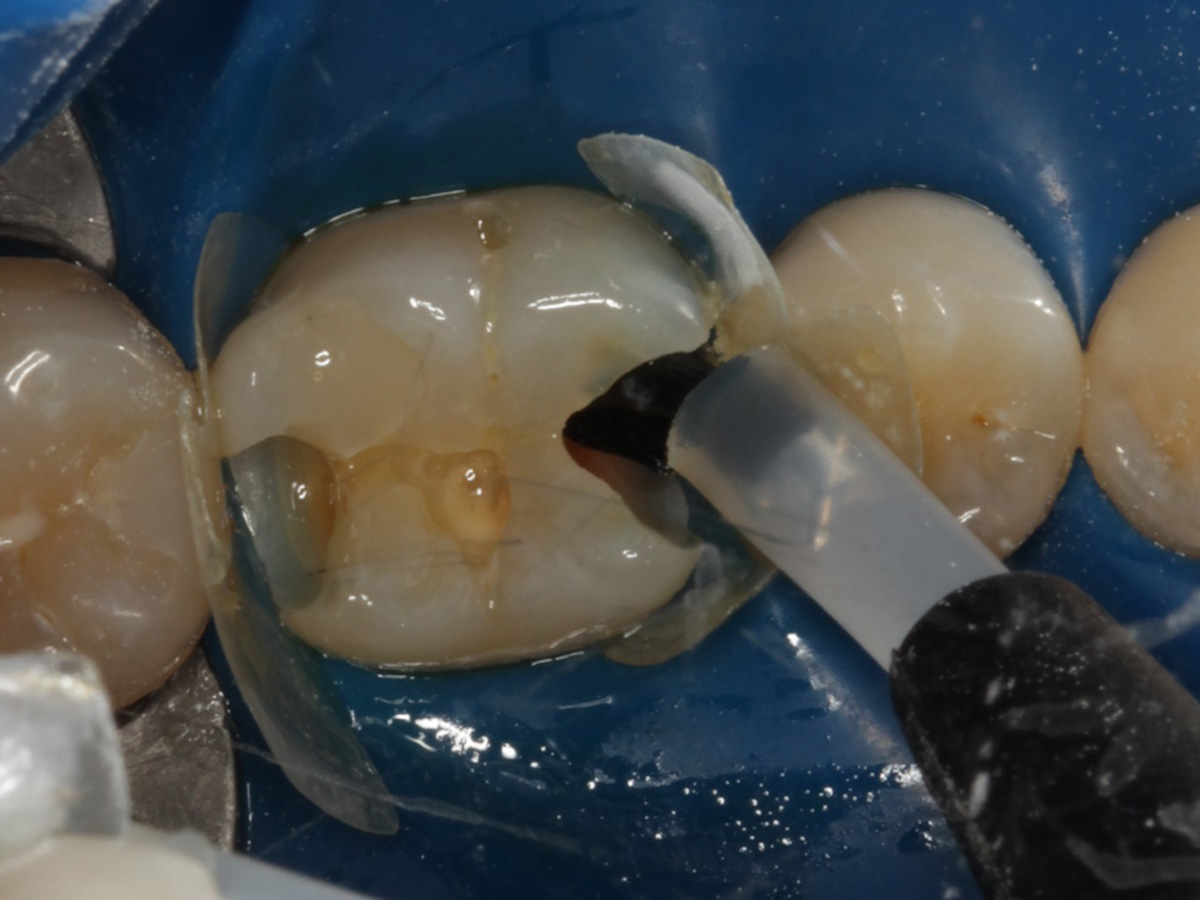

Abbildung 3

Schutz des Nachbarzahnes und des Kofferdams mit wiederverwandter Bioclear Biofit Matrize (gereinigt und sterilisiert); Separation zur Applikation der Matrize mit Heidemannspatel

Abbildung 4

Defektdarstellung; „Schutzmatrizen“ ideal als „Leitplanken“ bei der Zahnpräparation tief approximal bis in gesunde Zahnsubstanz